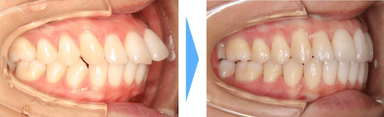

【出っ歯】

上の歯が前に突き出るので上唇は口角に向かって下がっているように見えます。下唇も口を閉じようとして力が入るため口角を引き下げます。

非抜歯で歯を動かすスペースを確保するためにIPRを行った症例です。

これ以外にも抜歯するほどではありませんが、IPRによって確保した隙間を利用して前歯を後ろに下げ、口元の印象を変化させることも可能です。

小臼歯の抜歯は行っていませんが、IPRを利用して前歯の位置を後ろに移動させたことで、治療後の口元を変化させることができました。

症例情報

【患者】20代女性

【主訴】上の前歯が出ている

【治療期間】1年8ヶ月 通院回数15回

【治療内容】親知らず2本を抜歯した後、マウスピース型カスタムメイド矯正歯科装置(製品名インビザライン 完成物薬機法対象外)を使用して主訴である上の前歯の突出の改善を行いました。

【費用】88万(税込)

【リスク】矯正歯科装置を付けた後しばらくは違和感、不快感、痛みなどが生じることがあります。

矯正中は矯正歯科装置が歯の表面についているため食物が溜まりやすく、また歯が磨きにくくなるため、虫歯や歯周病が生じるリスクがあります。

歯を動かすことにより歯根が吸収して短くなることや歯肉がやせて下がることがあります。

矯正歯科治療は公的健康保健の適応外の自費治療(自由診療)となります。